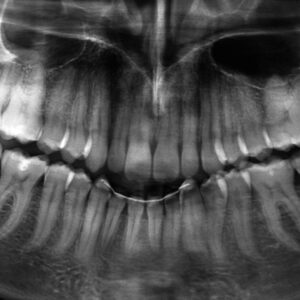

Impianti

L’implantologia dentale è una tecnica ampiamente diffusa che consente di sostituire i denti mancanti grazie all’uso di impianti studiati su misura per il paziente. L’impianto dentale deve integrarsi perfettamente all’osso mascellare o mandibolare e per questa ragione deve essere costruito con materiali biocompatibili. L’impianto dentale è un dispositivo medico necessario quando un dente naturale risulta...